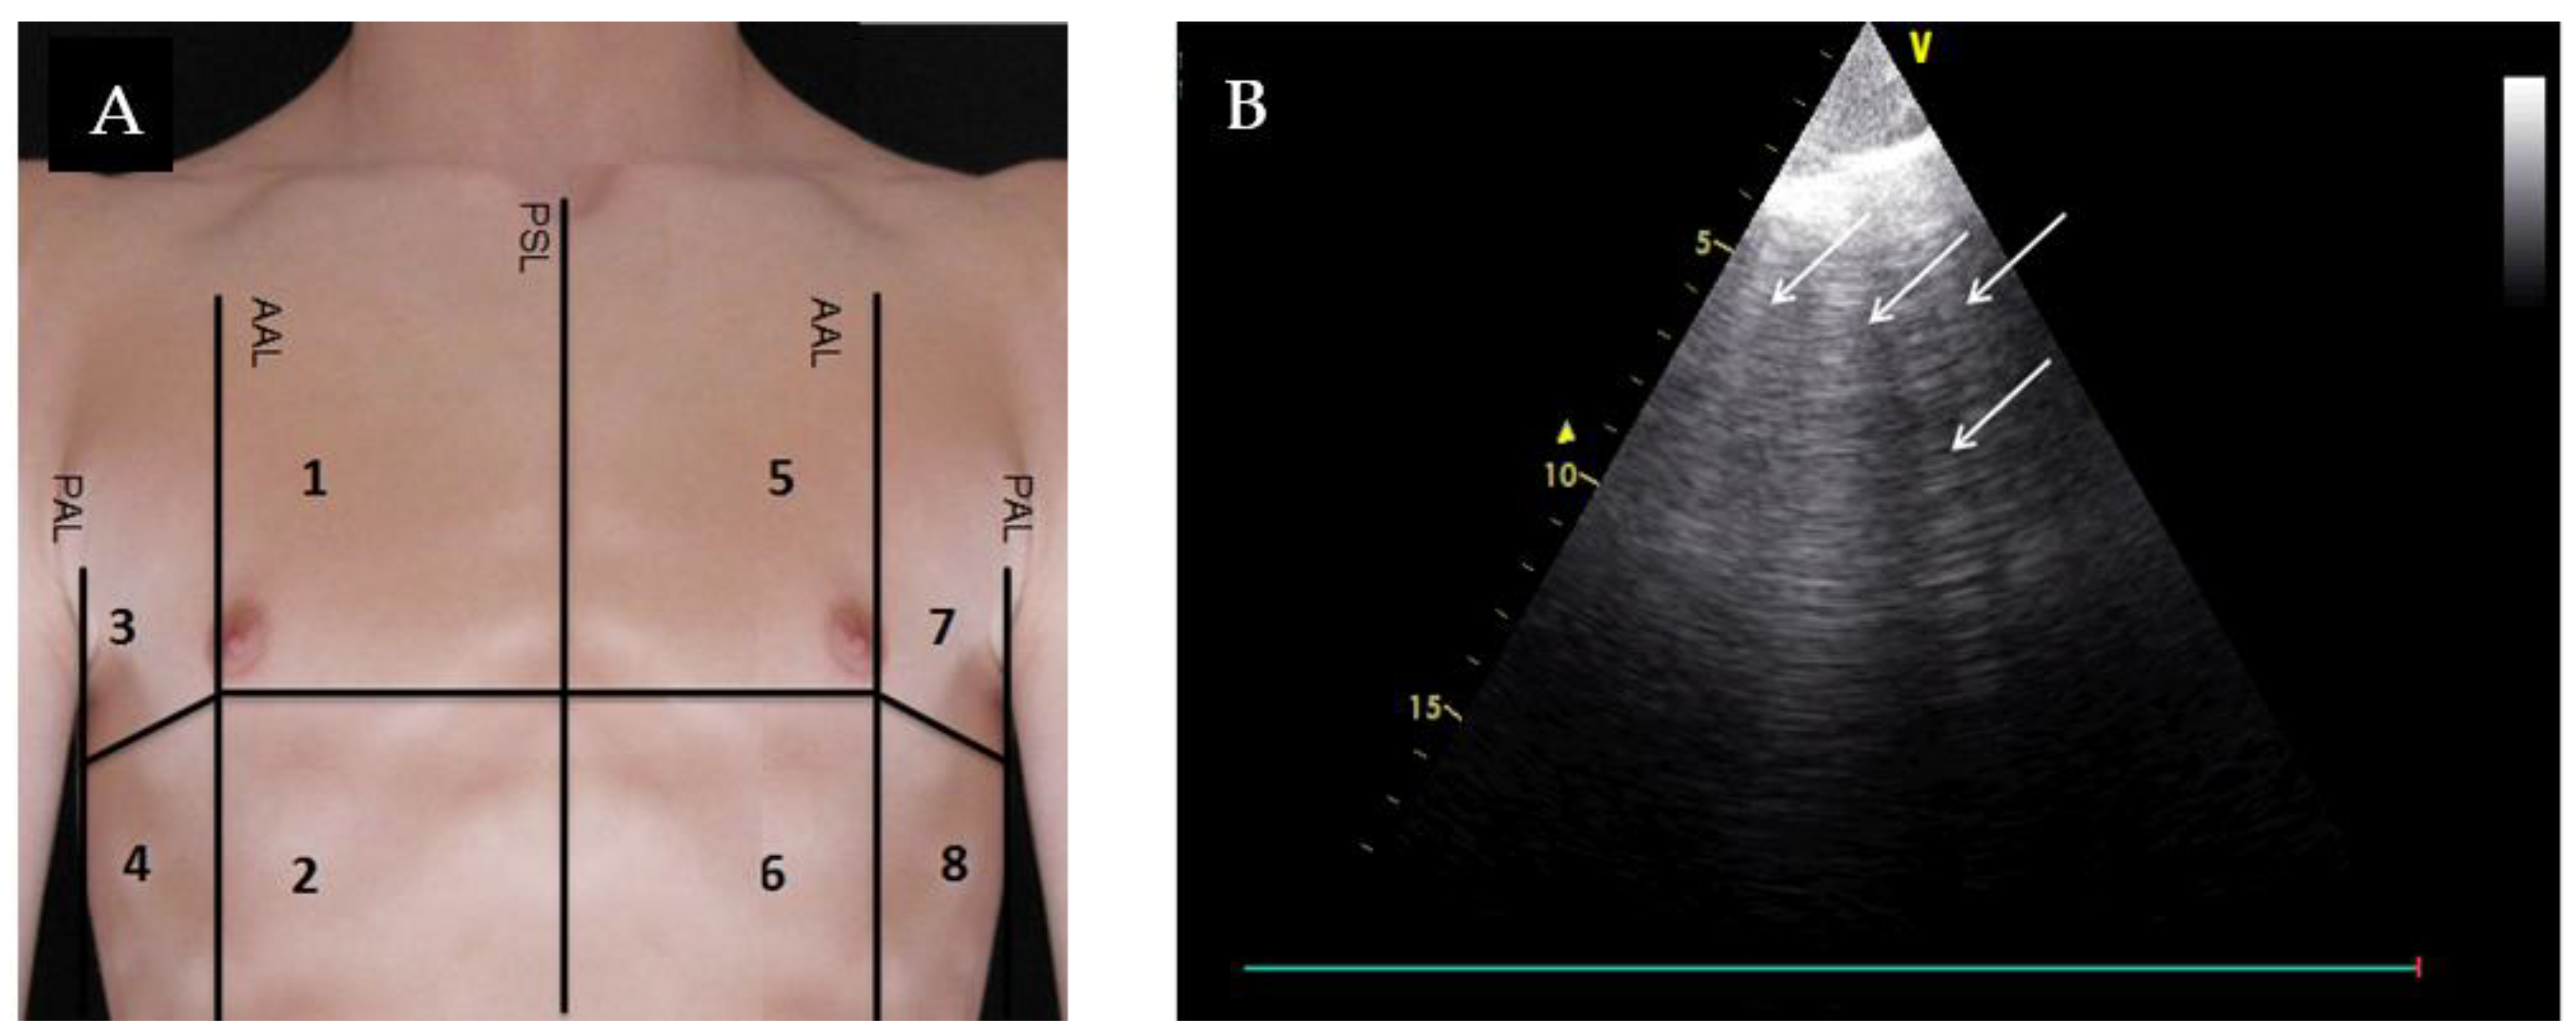

2. Materials and Methods